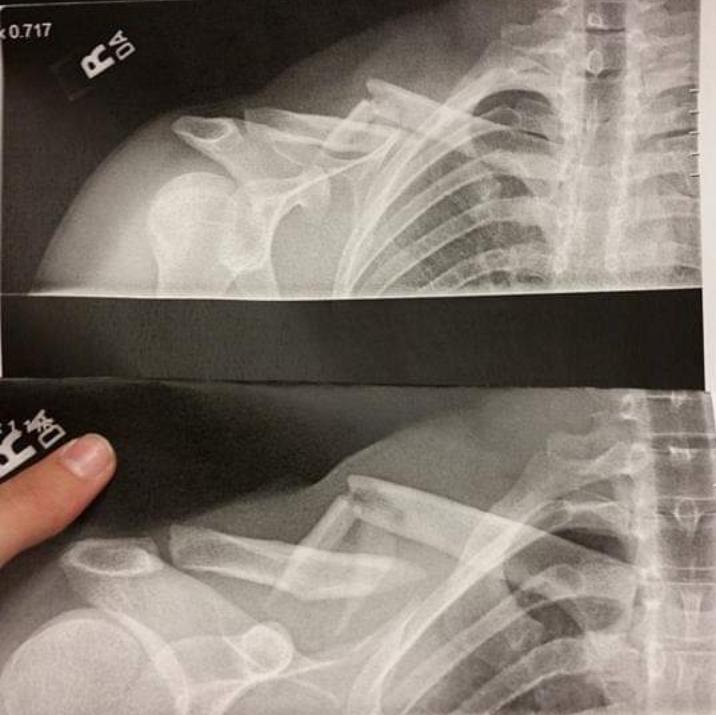

From www.jem-journal.com

Posterior Displacement of a Proximal Epiphyseal Clavicle Fracture Clavicle Injury From Weight Lifting It is an overuse phenomenon that causes tiny fractures along the end of the clavicle. The condition, sometimes called weightlifter's shoulder, is. The primary cause of distal clavicle osteolysis is repetitive microtrauma to the acromioclavicular (ac) joint during strength exercises, particularly those involving repetitive pushing or overhead. Distal clavicular osteolysis (dco) is an atypical injury occurring most often in athletes. Clavicle Injury From Weight Lifting.